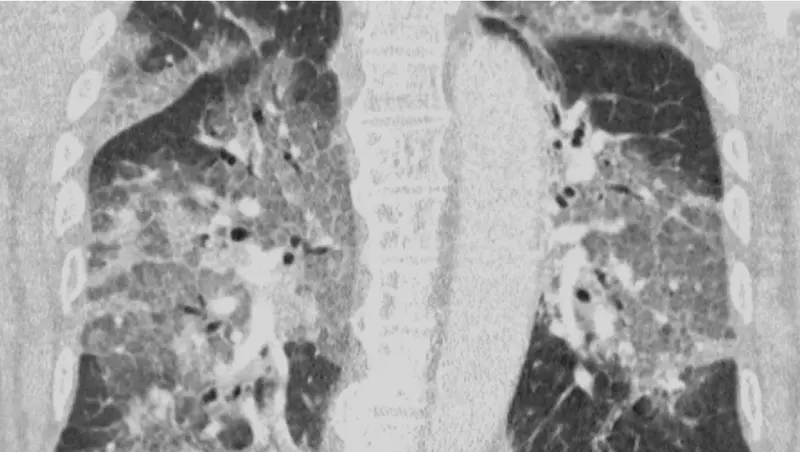

Ya se empiezan a notar las primeras consecuencias del miedo a los efectos secundarios de la vacuna de AstraZeneca contra la COVID-19, que está provocando el rechazo de algunas personas a recibir una dosis de la vacuna. Médicos holandeses han compartido las imágenes de las radiografías de los pulmones de un paciente, ingresado ahora en la UCI, que se negó a inyectarse la dosis por miedo. Los doctores intentan concienciar a las personas sobre lo que provoca el coronavirus y animar a la vacunación.

Los médicos también han publicado una carta abierta dirigida al ministro de Sanidad del país, Hugo de Jonge, sobre la paralización del uso de vacunas contra el coronavirus. En la carta relatan el ingreso en la UCI de un paciente no vacunado y cómo lucha contra le enfermedad con respiración asistida. "Oímos el tremendo pesar en su voz y la desesperación en sus ojos. El virus lo ha atacado y podría haberse evitado. Con su permiso, compartimos su escáner de pulmón. No es necesario ser un especialista en pulmones para reconocer la devastación, ni epidemiólogo para explicar los riesgos de no estar vacunado", cuentan.

Mediante las imágenes y las palabras publicadas pretenden mostrar a la población lo que la vacunación puede evitar. Además, han recalcado que “el riesgo de daño grave causado por el covid-19 es diez veces mayor para las personas de 40 años y 70 veces mayor para las de 60 años, que el riesgo de daño grave por trombosis".